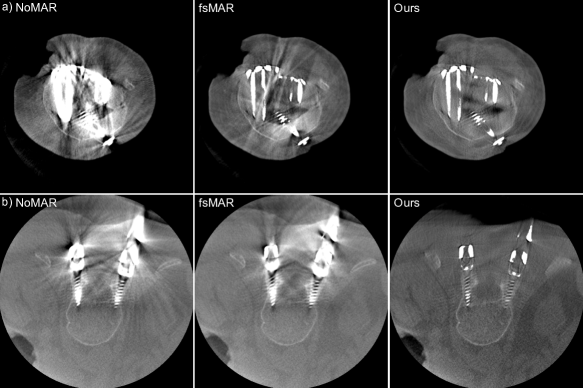

By examining the qualitative results and the corresponding SSIM line plots presented in Fig. 8 illustrating the results for test scans 1 to 5 and Fig. 9 illustrating the results for test scans 6 to 11 of the first fold, similar effects can be observed. It becomes apparent that for the majority of test cases the standard fsMAR, as well as the modified fsMAR, perform equally well, with a slight beneficial tendency for the proposed approach. The differences are that marginal, that they do not visually show up in the corresponding presented slices (cf. Fig. 8 & Fig. 9). This especially holds for scans comprising knees. However, investigating the qualitative results for test scans 2, 3 (Fig. 8), 6, 8, 9 (Fig. 9) and the example in Fig. 10, significant differences can be observed. In Fig. 8 at test scan 3 comprising a spine, it can be seen that the standard fsMAR is not able to segment the complete inserted pedicle screws, but only the associated heads. Due to that, only artifacts originating from the screws’ heads are reduced, whereas present beam hardening artifacts at the tips of the screws remain unchanged. In opposition to that, the proposed approach shows reduced artifacts throughout the complete size of the screws. Similar effects can be observed for test scans 8 and 9 in Fig. 9 where the segmentation of the standard fsMAR misses parts of the screws. For test scan 2 (Fig. 8) it becomes apparent that the streak artifacts, which originate from parts of K-wires, which lie outside the FoV of the reconstruction, are reduced more efficiently using the proposed segmentation approach. The represented slice for test scan 6 (Fig. 9) shows a similar case in which metal reaches from outside the FoV into the reconstruction. Whereas the standard fsMAR is able to fully segment the present metal plate and only an insufficient part of the metal lying outside and at the border of the volume, the modified fsMAR segments all present metal parts, thus achieving a more artifact reduced reconstruction. For both cases, a significant performance difference can also be seen in the corresponding line plots. However, similar to the quantitative results, the most significant difference between the two approaches can be seen for the presented test scan in Fig. 10. While for the shown slice, the standard fsMAR is not able to reduce any of the artifacts due to a failed segmentation, our approach nearly completely removes the present artifacts. Furthermore, the superior performance is not only reached in the single presented slice but rather holds for the complete set of slices.

Figure 11: Comparison of qualitative results for two clinical datasets. Row a) shows the MAR’s reconstructions for a clinical knee dataset and row b) for a clinical spine dataset.

When additionally examining the qualitative results for two clinical datasets, the same effects can be observed (cf. Fig. 11). Vanishing intensities in the metal objects lead to an under-segmentation of the implants by the standard fsMAR, thus reaching only a minor reduction of artifacts. The proposed approach however can segment the corresponding metal implants in 2D, thus reaching a significantly higher reduction of artifacts in both shown cases.